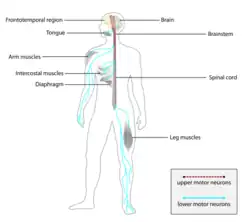

| Parts of the nervous system affected by ALS, causing progressive symptoms in skeletal muscles throughout the body[2] | |

Amyotrophic lateral sclerosis (ALS), also known as motor neuron disease (MND) or—in the United States and Canada—Lou Gehrig's disease (LGD), is a rare, terminal neurodegenerative disorder that results in the progressive loss of both upper and lower motor neurons that normally control voluntary muscle contraction.[3] ALS is the most common form of the broader group of motor neuron diseases.[8] ALS often presents in its early stages with gradual muscle stiffness, twitches, weakness, and wasting.[3] Motor neuron loss typically continues until the abilities to eat, speak, move, and, lastly, breathe are all lost.[3] While only 15% of people with ALS also fully develop frontotemporal dementia, an estimated 50% face at least some minor difficulties with thinking and behavior.[9] Depending on which of the aforementioned symptoms develops first, ALS is classified as limb-onset (begins with weakness in the arms or legs) or bulbar-onset (begins with difficulty in speaking or swallowing).[10]

ALS can be classified by the types of motor neurons that are affected.[2] To successfully control any voluntary muscle in the body, a signal must be sent from the motor cortex in the brain down the upper motor neuron as it travels down the spinal cord. There, it connects via a synapse to the lower motor neuron, which connects to the muscle itself. Damage to either the upper or lower motor neuron, as it makes its way from the brain to the muscle, causes different types of symptoms.[23] Damage to the upper motor neuron typically causes spasticity including stiffness and increased tendon reflexes or clonus, while damage to the lower motor neuron typically causes weakness, muscle atrophy, and fasciculations.[24]

The disorder causes muscle weakness, atrophy, and muscle spasms throughout the body due to the degeneration of the upper motor and lower motor neurons. Sensory nerves and the autonomic nervous system are generally unaffected, meaning the majority of people with ALS maintain hearing, sight, touch, smell, and taste.[3]